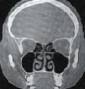

Tac cranio normale